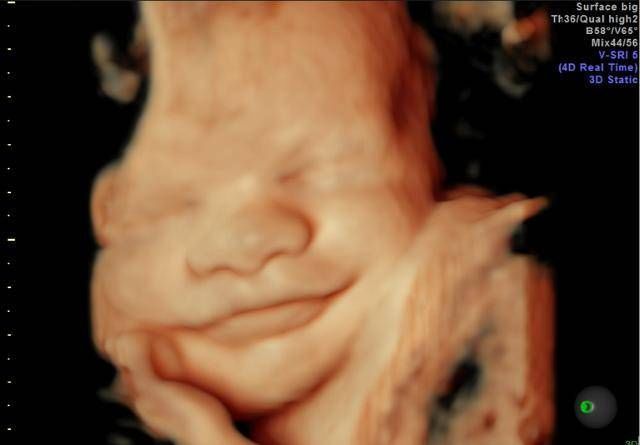

孕期产检,相信不少孕妈妈都很期待四维排畸这一项了,四维彩超排畸检查有不少准妈妈也想带着准爸爸进去,一同分享这其中的喜悦。

【 医生|为什么有些医院做四维彩超不让家属陪同这些原因,大家有权知道】小茹怀孕24周左右的时候,身边朋友提醒她这个时候需要做四维大排畸了,不仅能知道胎宝宝发育状况,还可以提前看到宝宝的长相。